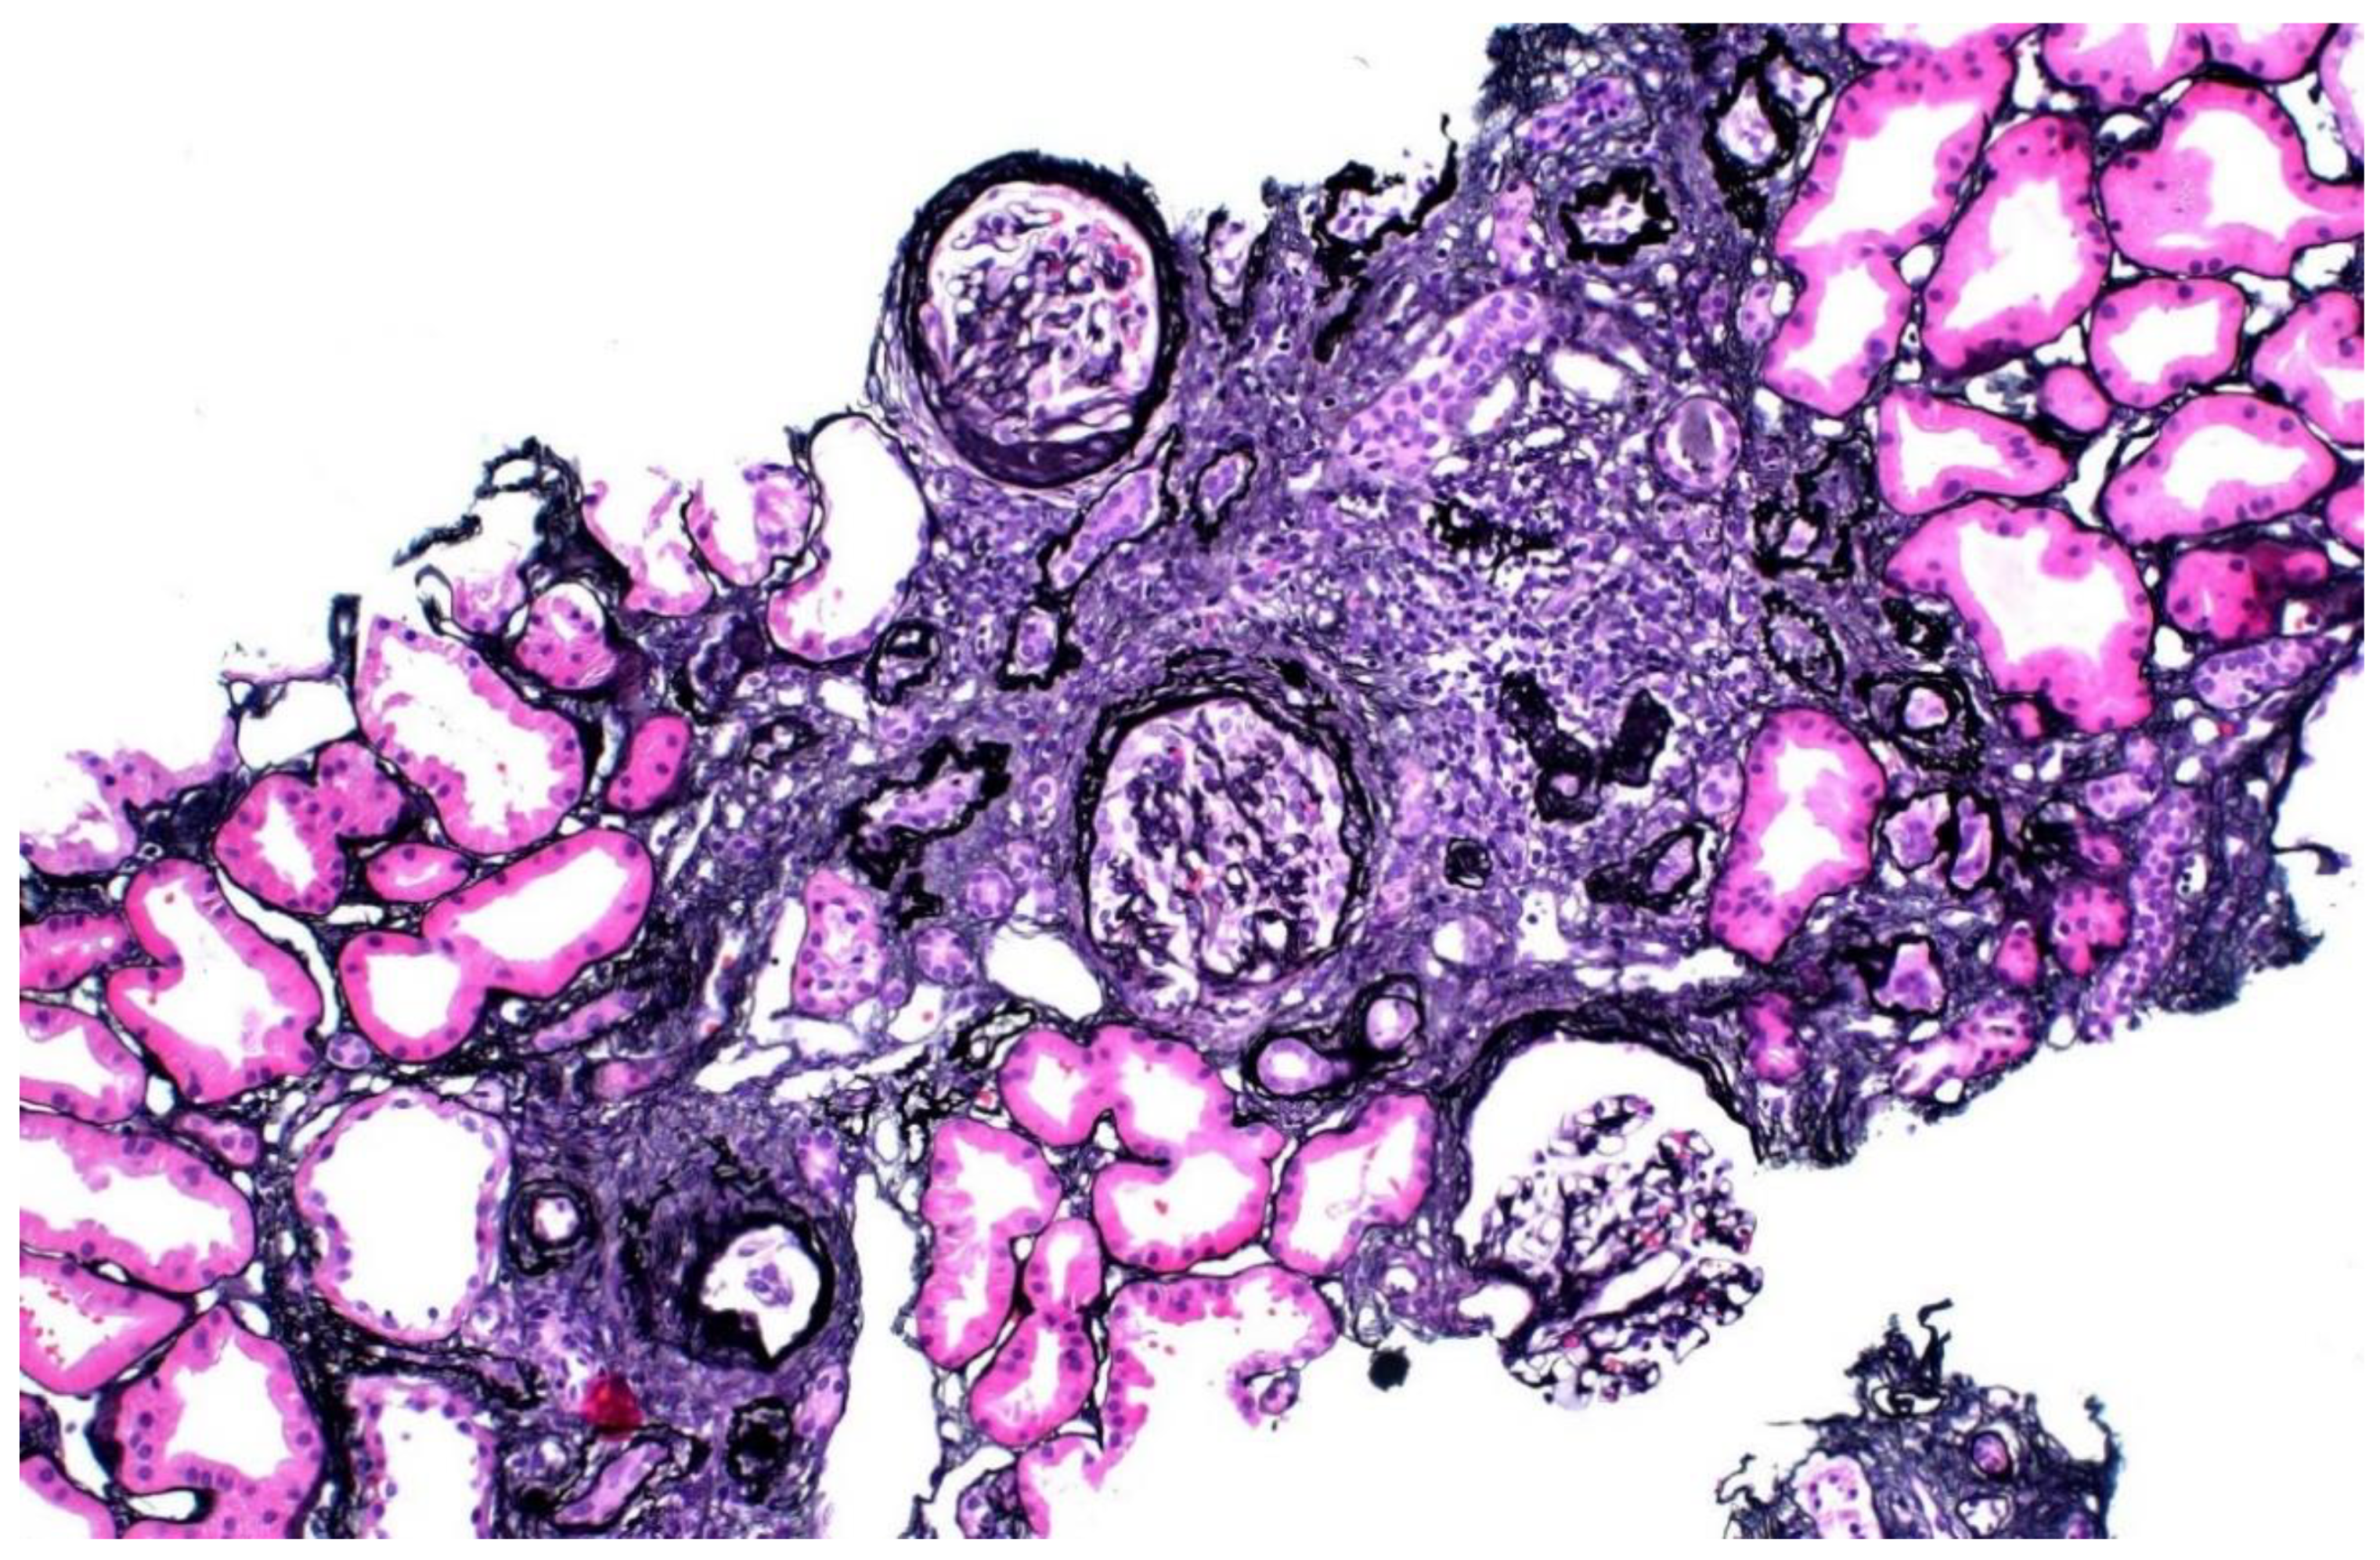

The donor’s serum creatinine stabilized at 1.7–1.8 mg/dL post-nephrectomy. Seen twice in the nephrology clinic during 2013, he subsequently stopped following up. Six years later, he was referred back because his serum creatinine was rising slowly and was up to 2.4 mg/dL. His younger sister had also developed CKD stage 4. He had developed gout and was started on allopurinol. The renal function and estimated glomerular filtration rate (eGFR) of the donor and his mother are shown in Figure 1. A kidney biopsy was performed, and he was referred for genetic testing. His kidney biopsy (Figure 2) showed focal global glomerulosclerosis, arteriosclerosis, tubular atrophy and interstitial fibrosis. Tubular basement membrane showed rupture with interstitial Tamm–Horsfall protein extravasation and associated mononuclear cell infiltration. Whole-exome sequencing showed a likely pathogenic missense variant in the UMOD gene (NM_003361.3:c.377 G>A p.C126Y) associated with autosomal dominant tubulointerstitial disease. The same genetic variant was also identified in his mother and sister. He was wait-listed for deceased donor kidney transplantation, and subsequently received a kidney transplant 10 years after having donated one of his kidneys.

Figure 2.

Kidney biopsy of donor 1, showing focal global glomerulosclerosis, arteriosclerosis, tubular atrophy and interstitial fibrosis.